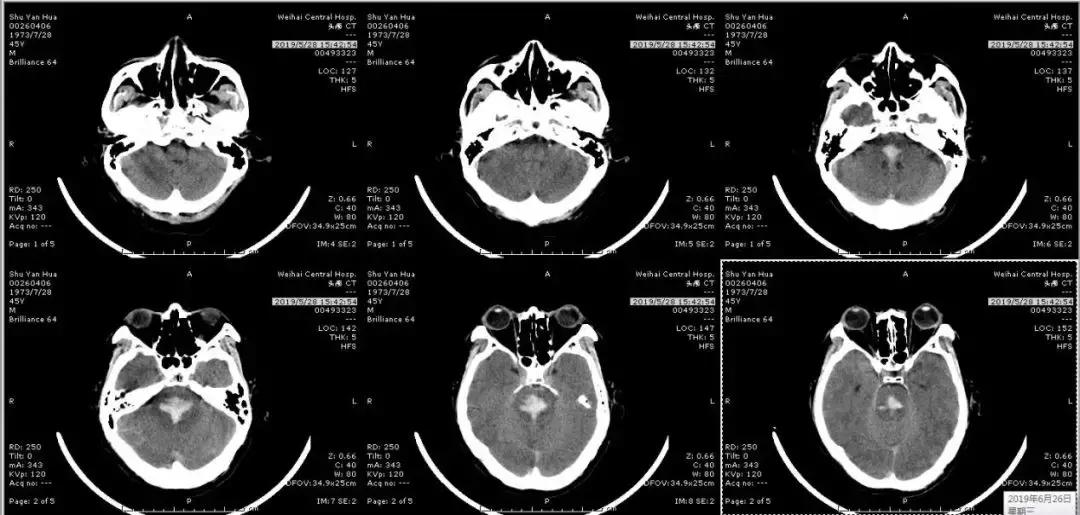

46岁的患者舒先生,5月24日上午突然头晕、呕吐,随即出现言语笨拙,四肢活动不灵,立即被送至威海市中心医院抢救。头颅CT检查示:脑干出血,出血量约3ml,期间患者持续内科保守治疗,但5月28日患者突然出现意识障碍加重、深度昏迷,呼吸急促、心率加快,复查头颅CT:脑干出血增多。出血量大于5ml,病情极其危重,已经危及生命。

(2019年5月28日入院后第4天血肿增多)